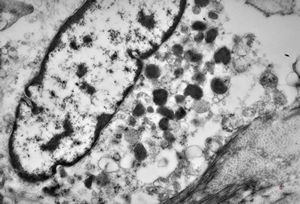

M, 43y. | myeloid leukemia … Auer bodies

M, 43y. | myeloid leukemia … Auer bodies

M, 43y. | myeloid leukemia … Auer bodies